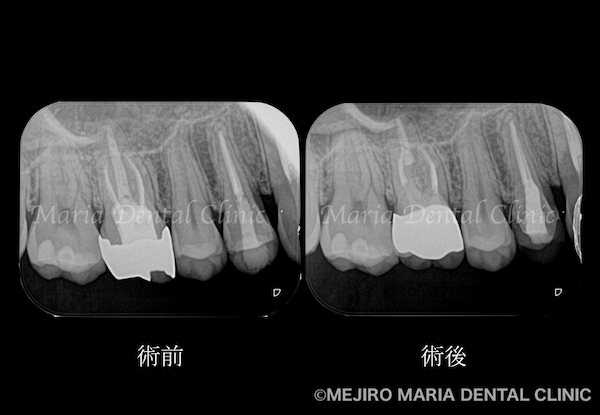

治療のコンセプトに沿って精密根管治療を2回で終了させ、暫間冠(仮歯)にて3ヶ月間の経過観察を行いました。3ヶ月後には症状は完全に消失、セラミック冠を装着して今後2年間の経過観察を行うこととしました。

精密根管治療から1年後の経過観察にて、患者様が初診時に訴えていた症状が消失していることを確認しました。

その結果、術前に見られた上顎洞に広がる不透過像(グレーの部分※膿)はほぼ消失していることが確認でき、予後は良好であると判断しました。